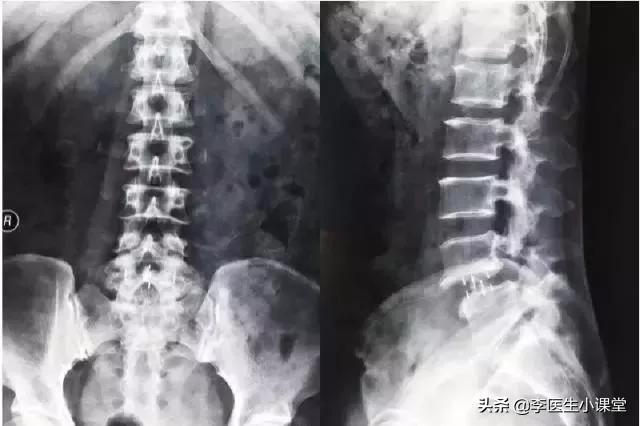

黄先生的腰椎X光片可以看出,他的腰椎确实有一定程度的突出。

检查发现:腰椎存在生理性弯曲,部分椎体边缘骨质增生及锐化,椎体无明显骨质破坏迹象,腰3/4及腰4/5椎体尖椎间盘突出,硬膜囊受压,对应椎管和椎间孔。通常,腰5/骶1椎顶椎间盘的形状一般是正常的。所示的小关节之间的关系没有明显的异常变化。

主诉:腰部疼痛、下肢麻木。

目前病史:腰痛间歇发作十余年问鼎娱乐下载入口,下肢麻木无力。